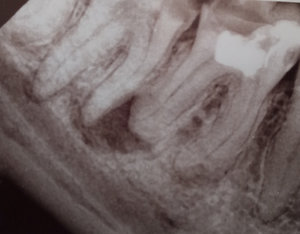

Отвалилась старая пломба, которую ставили девять лет назад. Пришел к стоматологу, она осмотрев сказала, что надо зачистить и заново запломбировать. Начав процедуру чистки, она попробовала пошатать зуб, потом сказала, что нужно сделать снимок. Снимок сделали, ее вердикт — надо удалять зуб, поскольку пошло воспаление вокруг корней, если его лечить со штифтами или еще как, через некоторое время он снова даст о себе знать и все равно придется удалить.